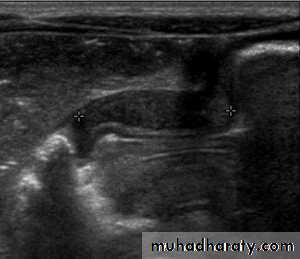

B.Duodenal loopHypertrophic pyloric stenosisCause:A. Congenital typeB. Adult type

Epidemiology:-Pyloric stenosis is relatively common and has a male predilection (M:F ~ 4:1), and is more commonly seen in Caucasians 4.

It typically occurs between the 4-8 weeks of life. There may be a positive family history.

Incidence of hypertrophic pyloric stenosis is approximately 2-5 per 1,000 births per year in most white populations.

In a normal situation, the pyloric muscle thickness (diameter of a single muscular wall on a transverse image) should normally be less than 3 mm (most accurate 3) and the length (longitudinal measurement) should not exceed 15 mm.